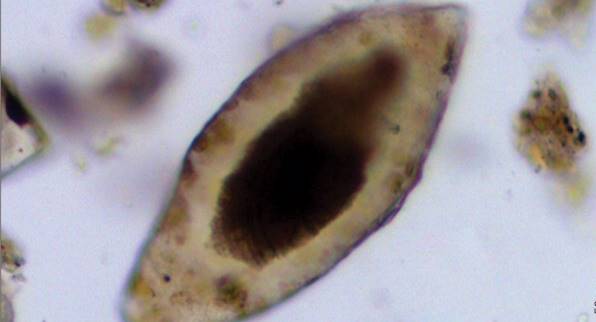

英國劍橋大學的生物人類學家 Piers Mitchell 在敘利亞一處古墓的某具孩童骨骸上,發現了血吸蟲(Schistosomiasis)的卵。血吸蟲病是目前仍存在、世界衛生組織宣佈的六大熱帶地區傳染病之一,幼蟲通常存活於淡水與淡水螺中,藉機接觸人體並鑽進人體生長。牠通常寄生於腎臟血管,造成血尿、貧血,有時造成膀胱癌;或是寄生在腸道,造成出血與貧血。